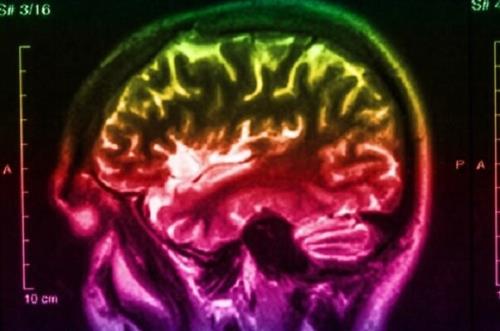

با رصد مغز مبتلایان به صرع؛

سلول های زمان در مغز انسان كشف شدند